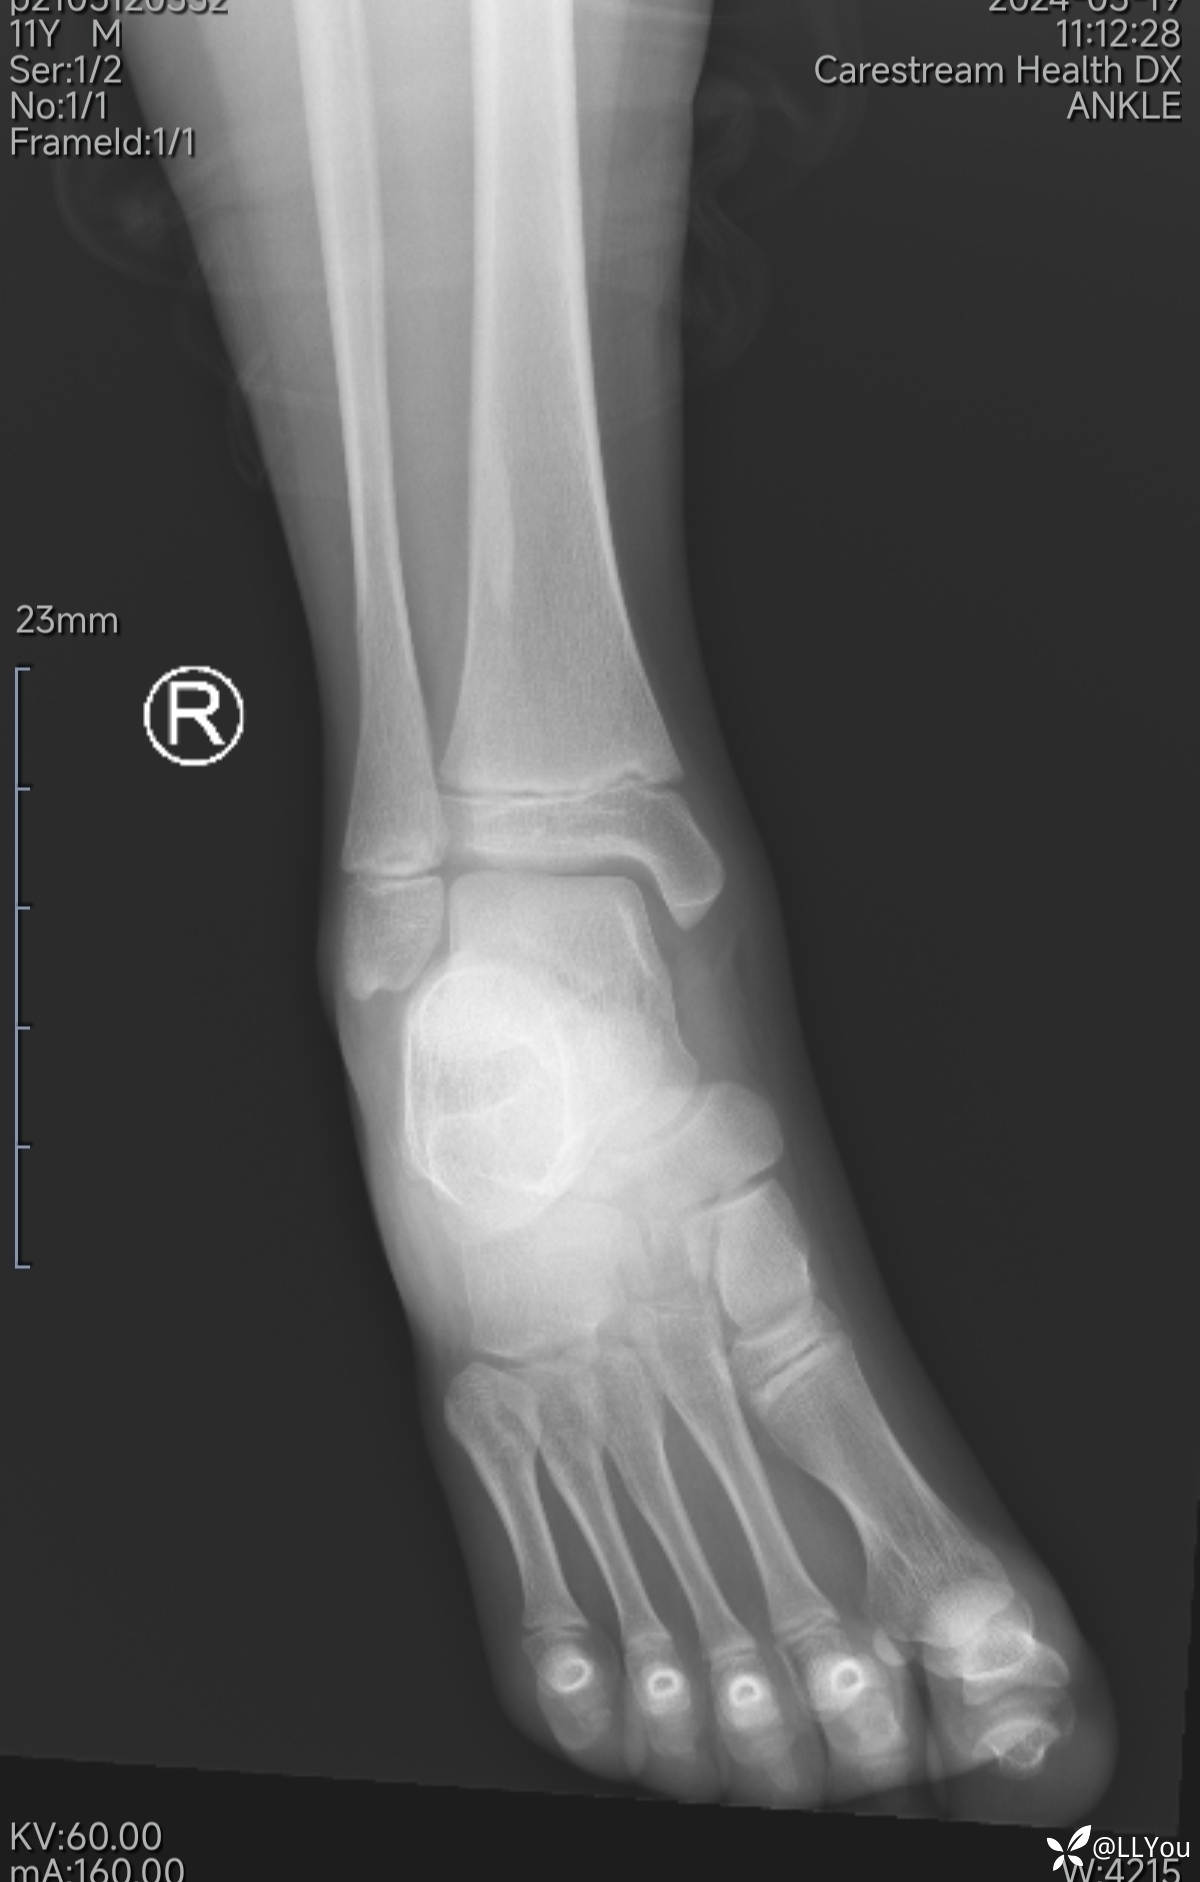

病人,男,11岁

踝关节外伤后肿痛2小时来诊

查体:踝关节轻度肿、压痛,活动稍受限。

踝关节X光片,见下图。